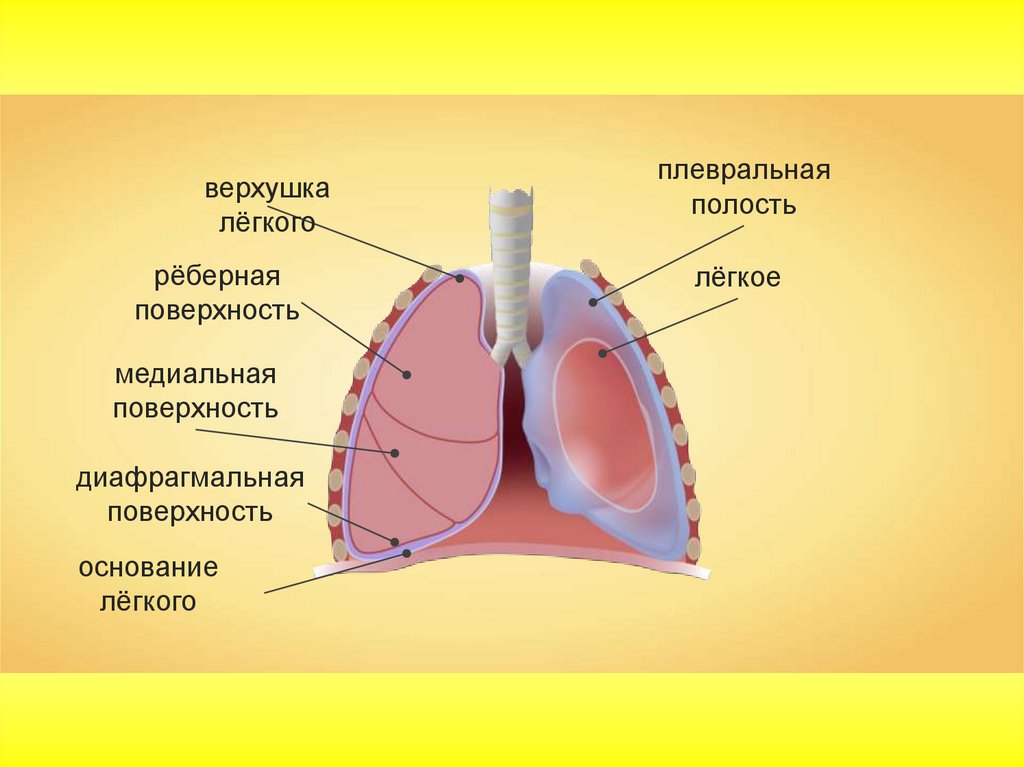

Анатомические изображения сегментов легких различных животных

Раздел: Другие животные